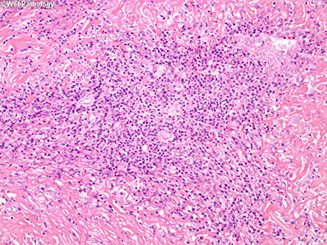

Medullary Carcinoma

1/20 thyroid cancers, may be inherited as autosomal dominant, derived from parafollicular C cells

Micro: Sheets of cells in amyloid stroma

- cells can be epithelioid or spindly and growing in nests or sheets; appearance of cells is variable

- Salt n peppa nuclei

IHC: (+) calcitonin, TTF-1, Cam5.2, AE1/AE3, mCEA, SYN, CHR, CD56, amyloid deposits Congo red +

Medullary ca c amyloid stroma